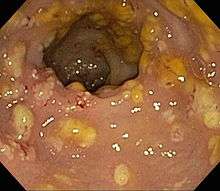

| Pathological specimen showing pseudomembranous colitis | |

Prior to the advent of tests to detect C. difficile toxins, the diagnosis most often was made by colonoscopy or sigmoidoscopy. The appearance of "pseudomembranes" on the mucosa of the colon or rectum is highly suggestive, but not diagnostic of the condition.[25] The pseudomembranes are composed of an exudate made of inflammatory debris, white blood cells. Although colonoscopy and sigmoidoscopy are still employed, now stool testing for the presence of C. difficile toxins is frequently the first-line diagnostic approach. Usually, only two toxins are tested for—toxin A and toxin B—but the organism produces several others. This test is not 100% accurate, with a considerable false-negative rate even with repeat testing.